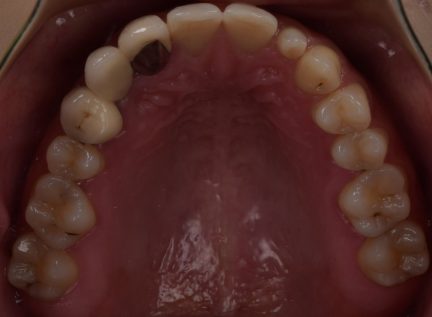

État final

- Relation de Classe I obtenue

- Guidage fonctionnel des canines des deux côtés

- Surplomb et recouvrement normaux obtenus

- Ligne esthétique du sourire obtenue

- Arcades harmonieuses obtenues

- Après traitement orthodontique, la partie supérieure droite 3, un implant posé et toutes les dents antérieures ayant reçu une restauration esthétique ont été utilisées.